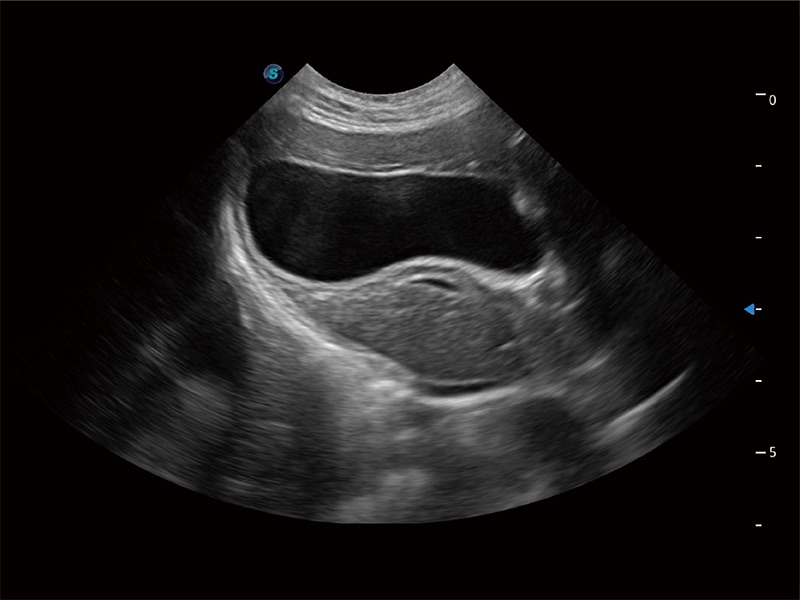

一键自动识别膀胱壁及自动测量膀胱容积,不受膀胱形状和大小的限制,帮助医生快速精准获得测量的数据。

ProPet 80 全新的动物超声智能软件和丰富的探头群,为动物医生提供了高清晰度和精细分辨率的图像,无论在宠物、马科、畜牧还是实验室动物等应用中都可以轻松应对,为您的日常工作带来满意的体验。